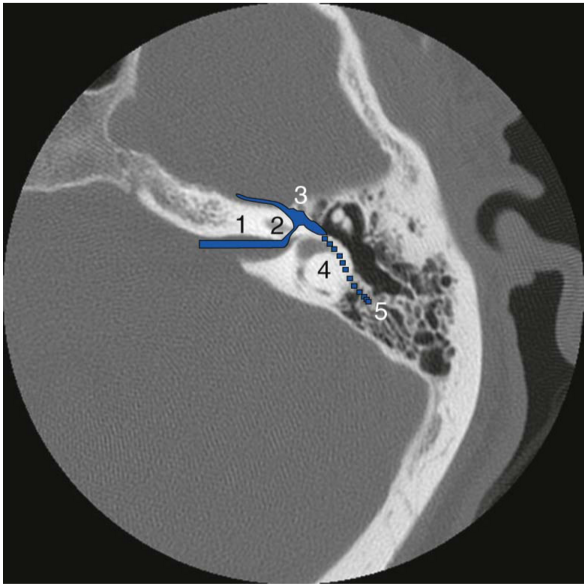

The site of facial nerve injury is in the perigeniculate region in most patients, possibly from tethering by the GSPN. Damage can also occur in the “horizontal” or tympanic segment and in the labyrinthine segment by direct injury or nerve edema (Figure 45-2). Chang and Cass reviewed surgical findings of four types of facial nerve pathology after temporal bone trauma. The authors’ review of 67 longitudinal fractures from three studies revealed that 76% of fractures had bony impingement or intraneural hematoma, and 15% had transection. The remainder had no visible pathology except neural edema. In contrast, of 11 transverse fractures reviewed, 92% were transected, and 8% had bony impingement.

Figure text: CT image of the facial nerve through the left temporal bone, segments include from proximal to distal; 1) meatal segment, 2) labyrinthine segment, 3) perigeniculate area, 4) “horizontal” or tympanic segment, and descending to the stylohyoid foramen as the 5) “vertical” or mastoid segment.